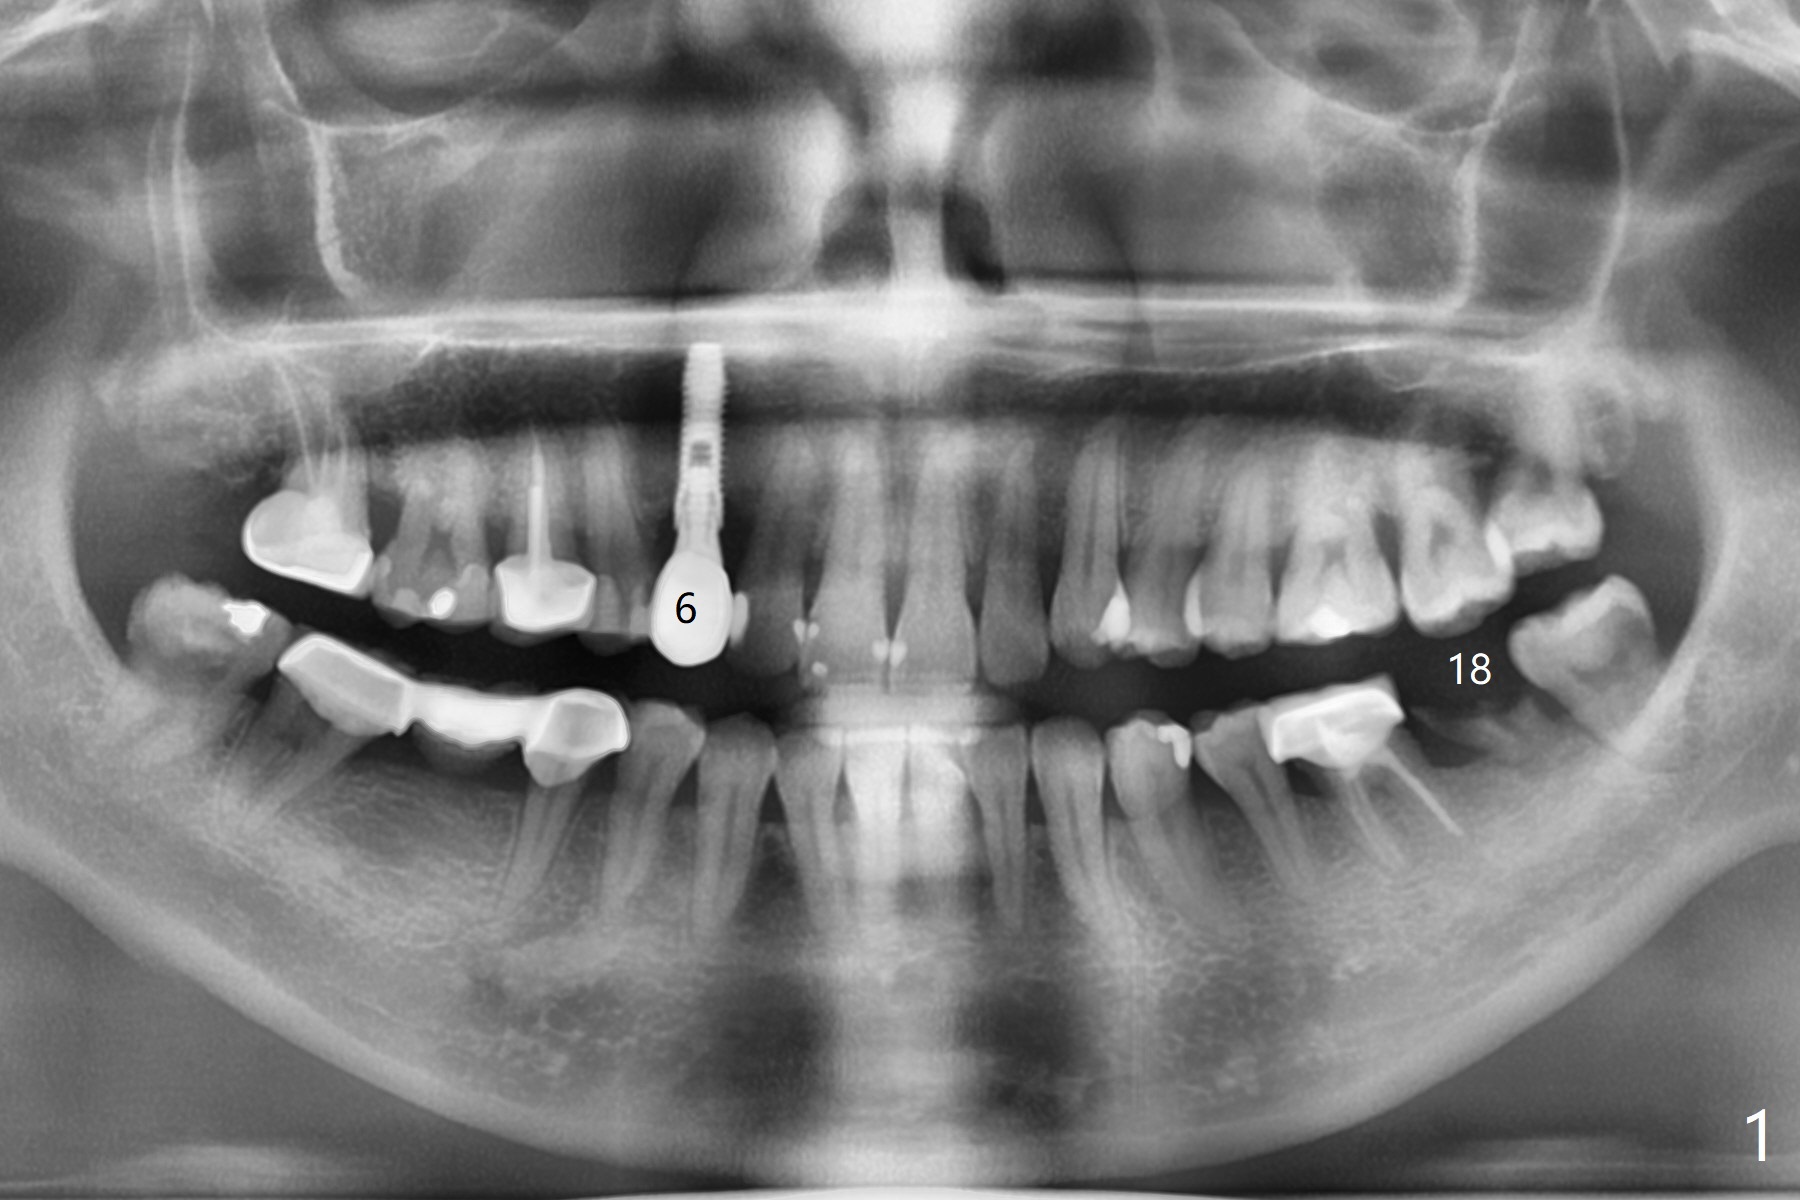

A 37-year-old woman, dental phobic, agrees to have implant at #18 (Fig.1). Since the mesiodistal and buccolingual widths of the edentulous area are moderate (Fig.2), a 5x8.5 mm implant seems to be big; a 4.5 mm one is better. The buccal and lingual bone resorption appears to be severe at #6 of the same patient postop.